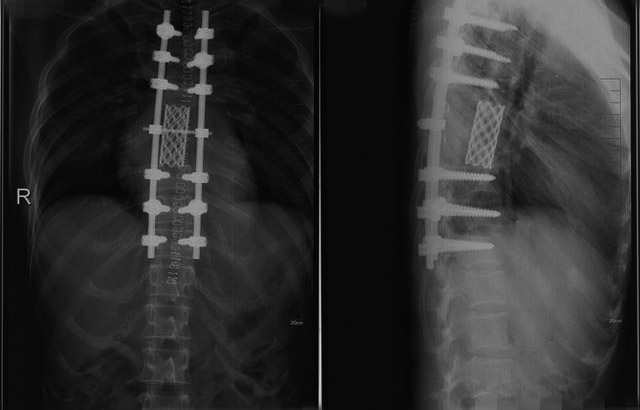

王某,男,78岁,去年国庆节前后出现轻微腰背部疼痛,没有在意,也没有进行治疗,症状时轻时重。 去年年底,王某突然出现双下肢无力,腰背部疼痛逐渐加重,10天后行走困难。 王某来到郑州市中心医院就诊时,已经不能行走,是坐着轮椅来的。王某入院后,进行了一系列检查。根据他的检查结果,我诊断是前列腺癌脊柱转移,他的前列腺癌指标PSA(前列腺特异性抗原)极高。王某发生前列腺癌脊柱转移,以胸椎为主,并压迫脊髓神经,导致瘫痪。 我给患者仔细讲述了病情以及导致瘫痪的原因,并讲明了手术治疗的必要性。 我带领郑州市中心医院脊柱外科医生,给患者实施了椎管减压和脊柱重建术。术后,患者不仅疼痛减轻,而且下肢活动功能明显改善,半个月后可以下床走路。 患者出院后,半个月来郑州市中心医院复查一次。我给予患者抑制肿瘤骨转移治疗,主要是进行比卡鲁胺抗雄激素治疗和二膦酸盐抗骨转移治疗。经过治疗,患者行走自如,能干家务活,每月的治疗费用不到1000元。患者多次来到我们医院进行复查,原有骨转移范围未扩大。 肿瘤转移(常见转移部位有脑、膈、淋巴结等)是恶性肿瘤的一个特征,并且是一个很不好的特征,而骨组织是恶性肿瘤转移的好发部位。肿瘤骨转移是指骨头以外的恶性肿瘤细胞,通过血流转移或者局部直接侵犯的方式转移到骨内。 肿瘤骨转移发生后,一部分患者无任何症状,但也有一部分患者会感到剧烈疼痛,发生病理性骨折、椎体塌陷,甚至压迫脊髓神经,引起瘫痪,让患者承受非常大的痛苦,严重影响患者的生活质量。 肿瘤骨转移及其造成的并发症也会导致治疗的难度增加及护理困难。让肿瘤患者少受肿瘤骨转移的“折磨”,保持不畏惧、积极治疗的心态,很重要。对肿瘤骨转移,早预防、早发现、早治疗是正确的做法。 虽然疼痛是肿瘤骨转移的一个主要症状,但是也有一部分肿瘤骨转移患者无任何痛苦的表现。除此之外,肿瘤骨转移患者还可能出现病理性骨折、高钙血症、肾结石等一系列并发症,如果发生脊柱转移,甚至会引起瘫痪。 大多数恶性肿瘤会出现骨转移,主要以前列腺癌、乳腺癌及肺癌为主。大约72%的前列腺癌患者、58%的乳腺癌患者、53%的肺癌患者会发生骨转移,其他常见的还有大肠癌、肾癌、胃癌、女性生殖系统癌等。 肿瘤发生骨转移的部位以脊柱最多,其次为肋骨、骨盆,而四肢骨少见。 一般来说,肿瘤骨转移早期是没有任何症状的,很多患者都是在肿瘤骨转移后期才出现剧烈疼痛,俗称“蚀骨之痛”。大多数肿瘤骨转移患者会有疼痛,疼痛是肿瘤骨转移患者面临的最大难题。在临床上,有些人是因为骨痛才去医院就诊,从而发现肿瘤骨转移;有些人发现肿瘤骨转移不是因为骨痛,而是因为骨折。 不同部位的肿瘤骨转移也有不同的疼痛症状:转移到脊柱时,表现为后背部正中或病变部位疼痛,压迫脊髓神经时可出现瘫痪;转移到肋骨时,表现为胸壁局限的、有明确压痛点的疼痛;而转移到骨盆、四肢骨时,表现为这些部位有局限性疼痛及放射性疼痛。 疼痛、骨折、瘫痪等一系列症状除了会给患者带来痛苦外,也会严重影响患者的饮食、睡眠质量。有些患者在经历疼痛→失眠→疲乏→疼痛→失眠→疲乏这样的恶性循环后,可能会产生不同程度的焦虑抑郁和营养不良。因此,对于出现肿瘤骨转移的患者来说,控制骨痛是一个非常重要的治疗目标。 肿瘤骨转移能否预防?答案是肯定的。 研究表明,双膦酸盐可以有效降低肿瘤骨转移相关并发症的发生率。多个临床试验结果显示,对于绝经后的乳腺癌患者,使用双膦酸盐能够降低乳腺癌骨转移的发生率,还有助于降低患者的死亡率。乳腺癌相关治疗指南指出,对于早期乳腺癌患者,建议应用双膦酸盐进行早期干预。 放射性核素锶-89有助于缓解患者骨痛和提高患者的生活质量。放射性核素锶-89虽然为全身给药,但是静脉注入后,在骨转移灶或骨肿瘤部位会出现较高浓度的聚集,是一种可有效治疗肿瘤的内照射治疗剂。前列腺癌、乳腺癌、肺癌等晚期肿瘤患者很容易发生骨转移,会有剧烈骨痛,严重影响患者的生活质量,而放射性核素锶-89可聚集于骨转移灶内,利用其发射的β射线进行内照射,达到杀死肿瘤细胞、抑制肿瘤骨转移的目的,并有效缓解疼痛,有效率达80%以上。一次治疗,止痛效果可以达3个月~6个月。 地诺单抗在防治肿瘤骨转移上也有很好的效果,它可以抑制肿瘤生长,使肿瘤区域骨化,对于高级别的、不可切除的、转移性的肿瘤疗效显著,主要用于实体瘤骨转移患者中骨骼相关事件的预防。地诺单抗适用于有骨质疏松症的绝经期妇女、雄激素阻断治疗所致的前列腺癌患者、芳香化酶抑制剂治疗所致的乳腺癌患者。 肿瘤骨转移能否早发现,答案也是肯定的。 恶性肿瘤患者应坚持每半年做一次骨扫描和PET-CT(正电子发射计算机断层显像)检查。SPECT-CT是单光子发射型计算机断层成像系统和X线计算机断层扫描成像系统一体化组合的影像诊断设备,能完美显示脏器组织的形态及功能变化,从而更早发现脏器功能及形态学变化,对某些疾病做出准确诊断,精准定位。PET-CT检查不仅适用于骨,而且适应于软组织(如肺部),和SPECT-CT检查的侧重点不一样。全身骨显像可以早期诊断骨转移瘤,比X线检查提前3个月~6个月发现病灶。 PET-CT是把正电子发射体标记的葡萄糖、氨基酸、胆碱、胸腺嘧啶及血流显像剂等药物作为示踪剂,以解剖图像的方式,用分子水平显示机体及病灶组织细胞的代谢、功能、血流、细胞增殖和受体分布情况,为临床提供更多的生理和病理方面的诊断信息,故也称为分子显像。 PET-CT有以下作用:可以对肿瘤的良性、恶性进行鉴别诊断;进行肿瘤的临床分期及治疗后再分期;对肿瘤治疗过程中的效果进行监测,对治疗后的效果进行评价;在肿瘤患者随访过程中监测肿瘤复发及转移;对肿瘤治疗后的残余与治疗后的纤维化或坏死进行鉴别;已发现肿瘤转移而临床需要寻找原发灶。患者进行PET-CT检查,有利于医生制定最佳治疗方案,发现早期肿瘤癌前病变,以获得治愈的机会。 除此之外,还可以通过监测血中碱性磷酸酶,尽早发现可能存在的骨转移。